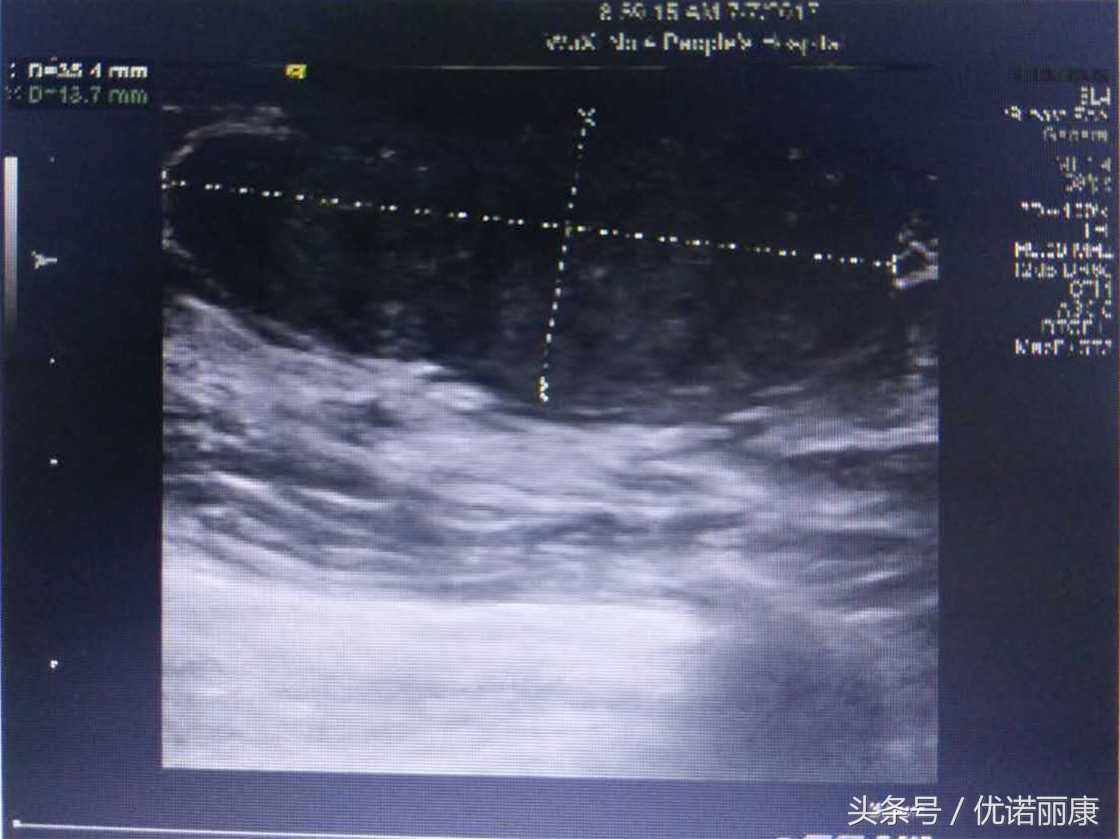

良性纤维腺瘤

肿块35x14mm,边界清,形态规则,内部回声欠均匀,内见少量血流信号,分级2级。